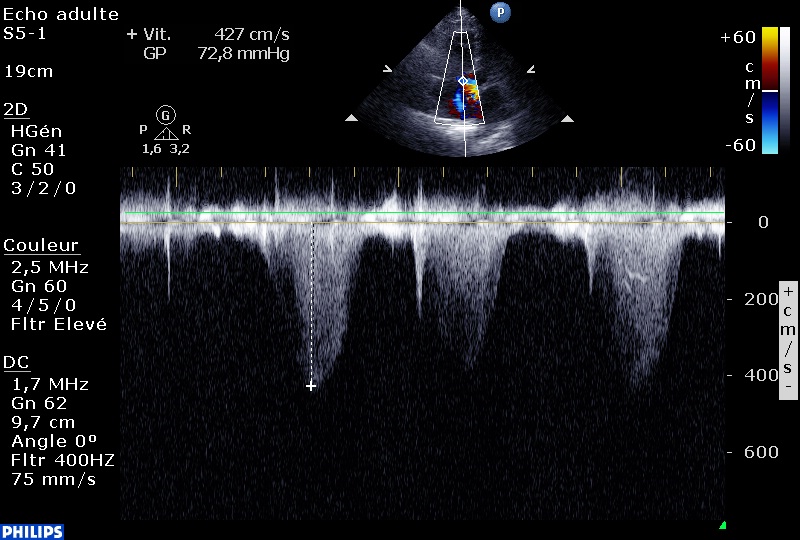

Chez ce patient hospitalisé pour détresse respiratoire, l’échographie trans-thoracique au lit retrouve des caractéristiques de cœur pulmonaire (sub?) aigu avec:

Une Hypertension artérielle très sévère à 85 mmhg, calculée sur l’insuffisance tricuspide :

Des cavités droites modérément dilatées mais une fonction ventriculaire droite conservée (pour développer une insuffisance tricuspide aussi véloce, la fonction VD est nécessairement conservée). La veine cave inférieure est fine, le VD n’est pas hypertrophié, l’artère pulmonaire est peu dilatée.